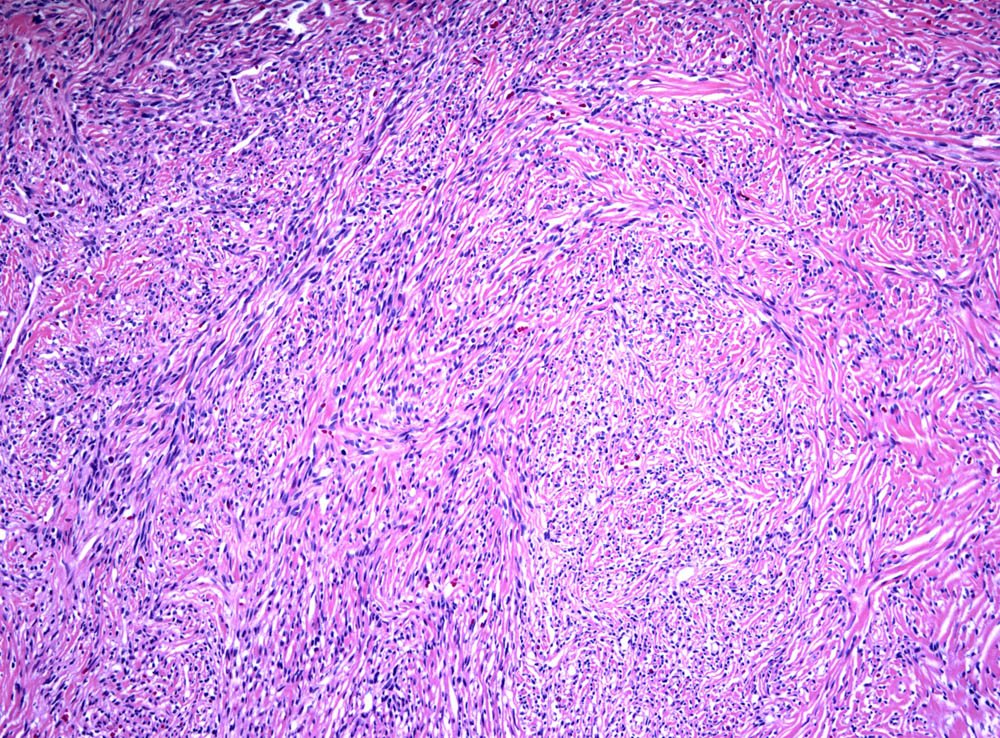

Case: SpinalMass

Final Diagnosis: